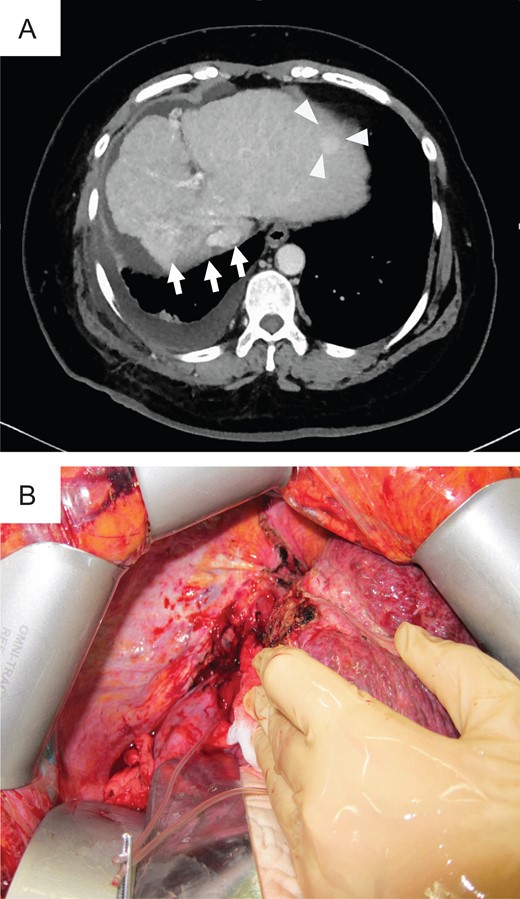

In 2014, she was administered CIRT with a total of 60 Gy (relative biological effectiveness) given in four fractions because of rapidly enlarged tumor with segmental portal vein invasion, as shown on contrast-enhanced computed tomography. Before admission, CT revealed a new recurrence tumor in the lateral segment of the left lobe (Fig. 1A). The irregular surface and unsmooth liver edge also showed LC. Furthermore, severe atrophy was obvious at the CIRT area (Fig. 1A). Because of the new lesion in the left lobe located close to the heart and the underlying liver failure with C-P grade B (9 points), LDLT was performed with an extended left lobe graft from her son in 2015. During surgery, strong adhesion between the thoracic diaphragm and the irradiated lesion in Segment 7 was observed, which resulted in difficulty with adhesiolysis (Fig. 1B). If we preserve the diaphragm, it might be injured irradiated liver during adhesiolysis. We intensively choose a part of diaphragm resection with liver, also protected inferior vena cava (IVC) from injury during resection of diaphragm. We checked where the IVC existed in the thoracic cavity and preserved the IVC above the liver, encircling the right hepatic vein (RHV) after mobilization of the liver. The diaphragm was then repaired directly by suturing. After reconstruction of the hepatic vein (HV), portal vein (PV), hepatic artery and bile duct, we successfully finished the operation. The surgery took over 11 h to complete, and the total amount of blood lost was 2500 g with 10 units of fresh-frozen plasma transfusion (FFP). The specimens showed no HCC recurrence in the CIRT area but did show severe fibrosis (Fig. 2).

Preoperative photograph and intraoperative images of case 1. (A) Liver atrophy was noted in the CIRT area (arrow), and a new lesion (triangle) was noted in the left lobe on preoperative CT. (B) Intraoperative imaging showed strong adhesion between the thoracic diaphragm and the CIRT area.